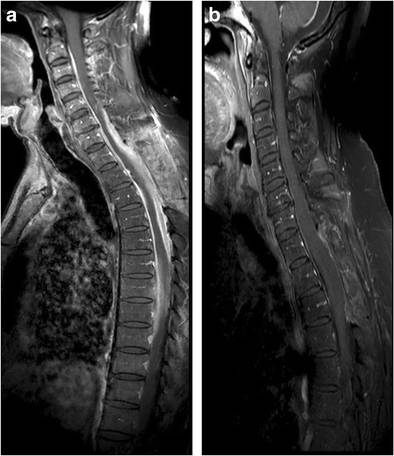

图12:IgG4相关性肥厚性硬脊膜炎患者;a:可见C2-T9水平弥漫硬脊膜增厚强化;b:治疗6月后病灶较前好转